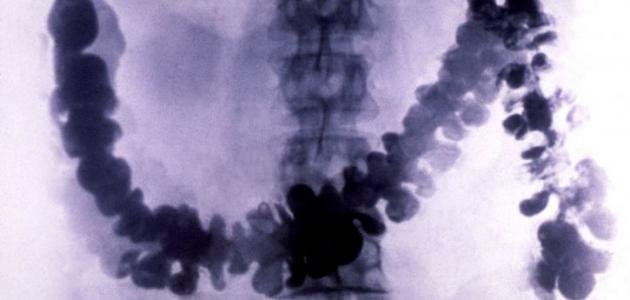

يُعرّف تضخّم القولون (بالإنجليزية: Megacolon) بحدوث تمدّد غير طبيعيّ في القولون، ويتمّ استخدام مصطلح تضخم القولون السميّ (بالإنجليزية: Toxic megacolon) للتعبير عن خطورة هذه الحالة، وعلى الرغم من أنّ مشكلة تضخّم القولون تُعدّ من الحالات الصحيّة النادرة إلّا أنّها قد تكون مهدّدة لحياة الشخص المصاب، وتتمثل هذه المشكلة بالتهاب وانتفاخ الطبقات الداخليّة للقولون ممّا يؤدي إلى توقف عمل القولون، وفي بعض الحالات الشديدة قد يحدث تمزّق في القولون، والذي بدوره قد يؤدي إلى تعفّن الدم (بالإنجليزية: Sepsis) والوفاة.[١][٢]